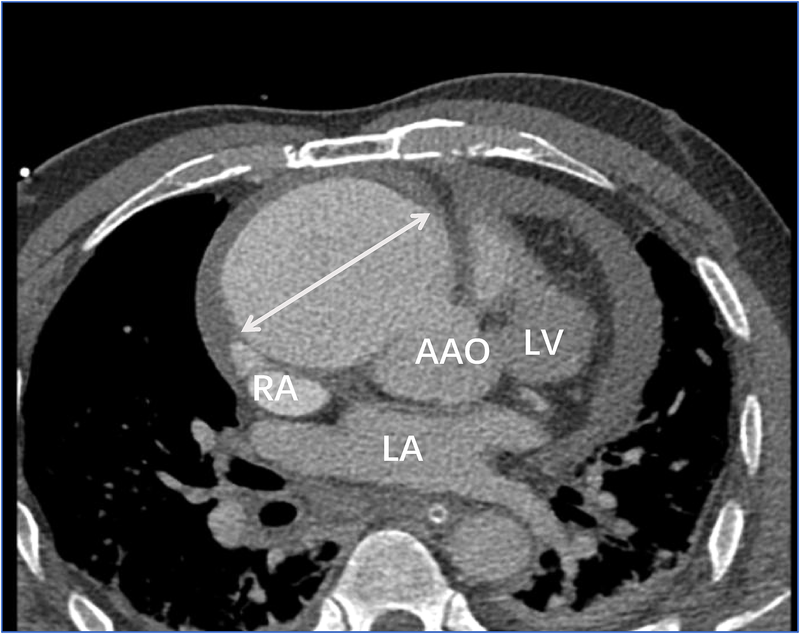

Transthoracic echocardiography (Figure 1) revealed a tumor-like abnormal hypoechoic area measuring approximately 70 mm × 66 mm × 75 mm located about 1 cm from the aortic valve annulus, extending outward from the sinus. This mass communicated with the aorta through a 15 mm × 9 mm defect, with blood flow directed from the aorta to the right coronary artery. Contrast-enhanced computed tomography angiography (Figure 2) confirmed a spherical dilatation (6.0 cm × 7.5 cm) in the right anterior aspect of the ascending aorta. A defect measuring approximately 1.1 cm in diameter was seen in the anterior aspect of the ascending aorta, connecting with the spherical dilation. Compression was noted on the ascending aorta root, aortic sinuses, and right atrium.

Figure 2. Contrast-enhanced computed tomography angiography confirmed a spherical dilatation (6.0 cm × 7.5 cm) in the right anterior aspect of the ascending aorta (white arrow). LA, left atrium; LV, left ventricle; RA, right atrium; AAO, ascending aorta.

Figure 8. Computed tomography angiography (CTA) suggests localized nodular protrusions in the right coronary sinus, measuring approximately 1.4 × 1.2 cm (black arrow). LA, left atrium; LV, left ventricle; RA, right atrium; AAO, ascending aorta.